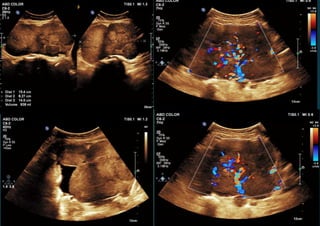

Exampleswhere Simple descriptor don’t apply

<10cm

Example 1

Simplerules: BENIGN

Mucinous cystadenoma

Example 2

Simple rules:MALIGNANT

Metastasis from bowel primary